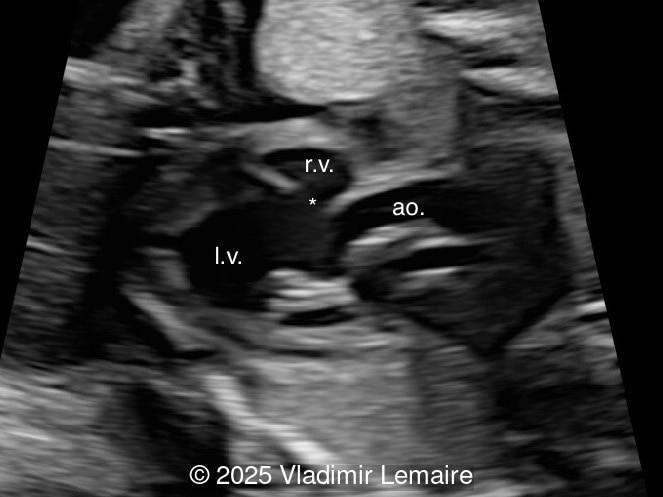

Left ventricular outflow tract view.

Image 4 Left ventricular outflow tract view.

The size of the great vessel arising from the right ventricle should be evaluated for the presence of stenosis, which is a common association. The severity of right outflow tract obstruction directly correlates with the size of the right ventricle and the ventricular septal defect. Occasionally, pulmonary or aortic atresia can be found.